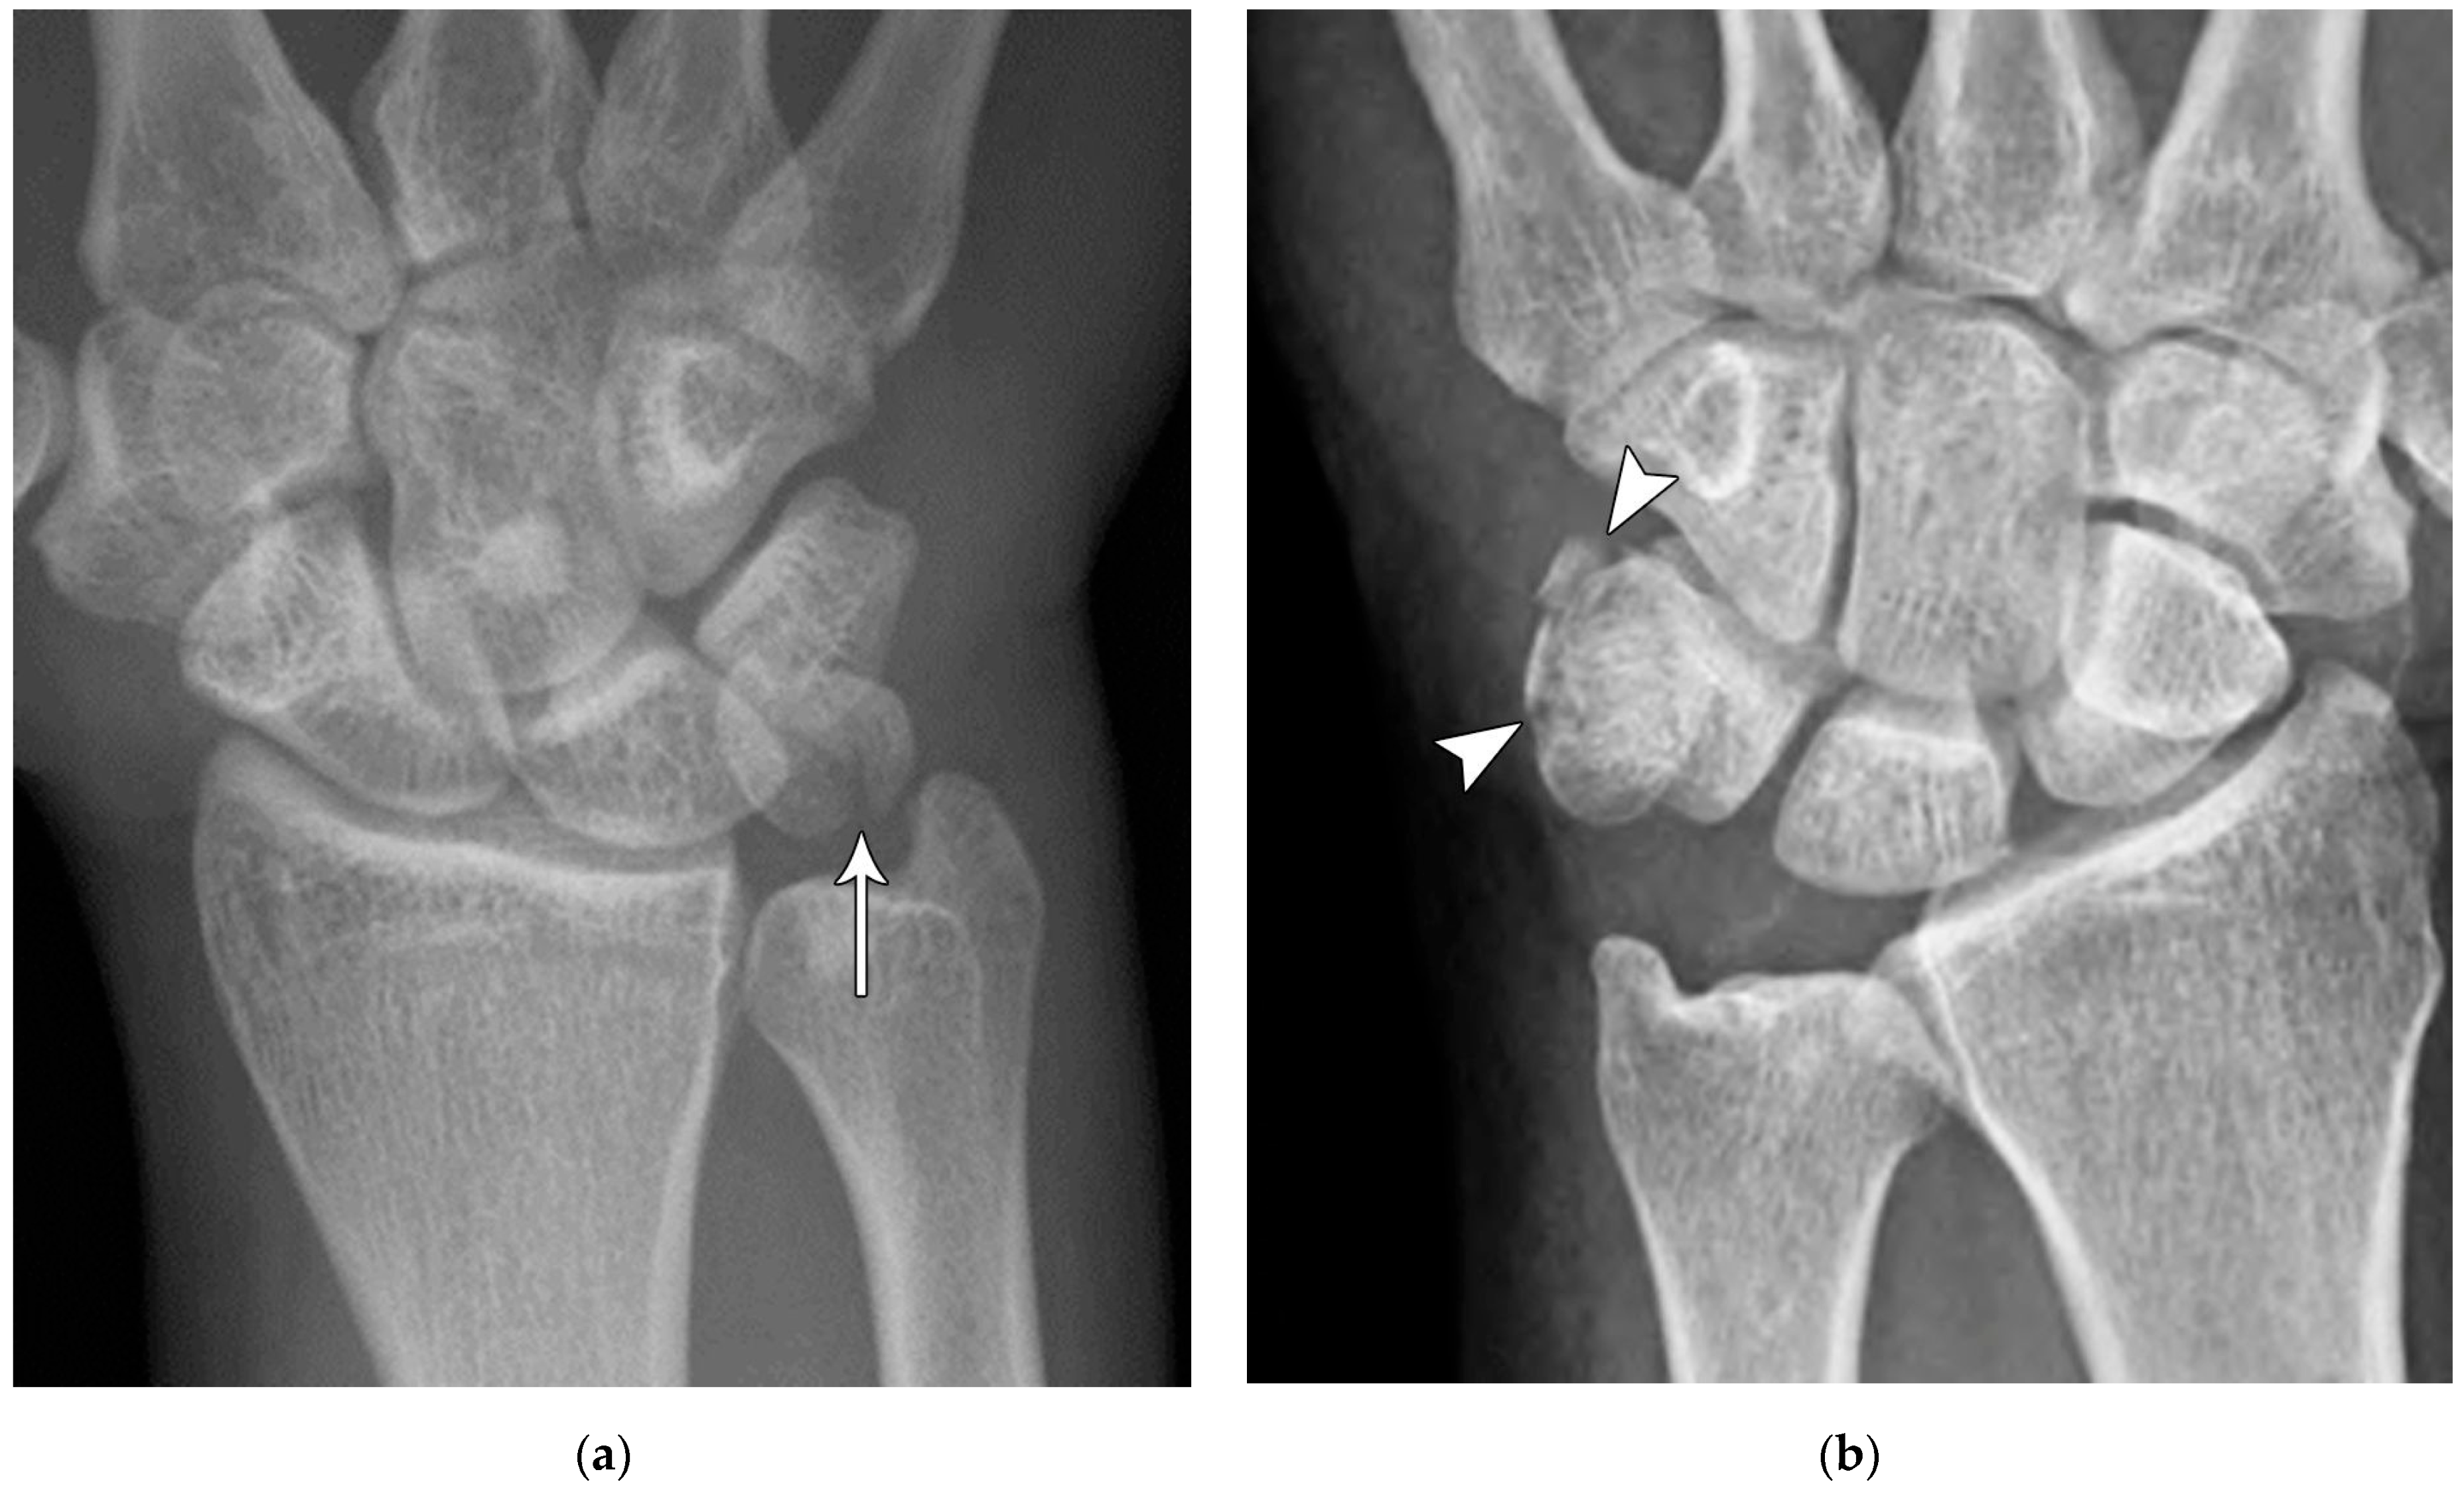

Figure 5. (a) PA radiograph showing marked sclerosis (arrow) of the proximal pole of the scaphoid after a scaphoid fracture. (b) Coronal reformatted CT in a different patient showing sclerosis (arrow) of the proximal pole of the scaphoid after a scaphoid fracture, indicating osteonecrosis.

Common scaphoid fracture complications include avascular necrosis and nonunion [10]. Avascular necrosis is a dreaded outcome resulting from the loss of the proximal arterial supply due to the distal entry point of nutrient vessels. This retrograde perfusion of the proximal pole makes it vulnerable to losing its vascular supply when fractured. Sclerosis of the proximal pole indicates osteonecrosis (Figure 5). With scaphoid nonunion, biomechanical alterations contribute to rapidly progressive degenerative arthritis and instability referred to as scaphoid nonunion advanced collapse (SNAC) [16]. Nonunion occurs in 5–10% of cases and has a higher incidence in displaced fractures (Figure 6). During wrist extension, the distal scaphoid fragment rotates into flexion while the proximal scaphoid fragment extends with the lunate. The resultant abnormal contact between the distal fragment and radius begins the first stage of degenerative collapse. This progresses into the second stage as scaphocapitate osteoarthritis develops and finally to the third stage with progression to capitolunate osteoarthritis and proximal radial migration of the capitate dorsal to the lunate. Treatment of SNAC wrists, depending on the degree and severity of the osteoarthritic collapse, includes scaphoidectomy with four-corner arthrodesis or wrist fusion [17]. Four-corner fusion helps reduce joint pain while maintaining some range of motion, as opposed to total wrist fusion (Figure 7). Another option is proximal row carpectomy with resurfacing capitate pyrocarbon implant placement [18].